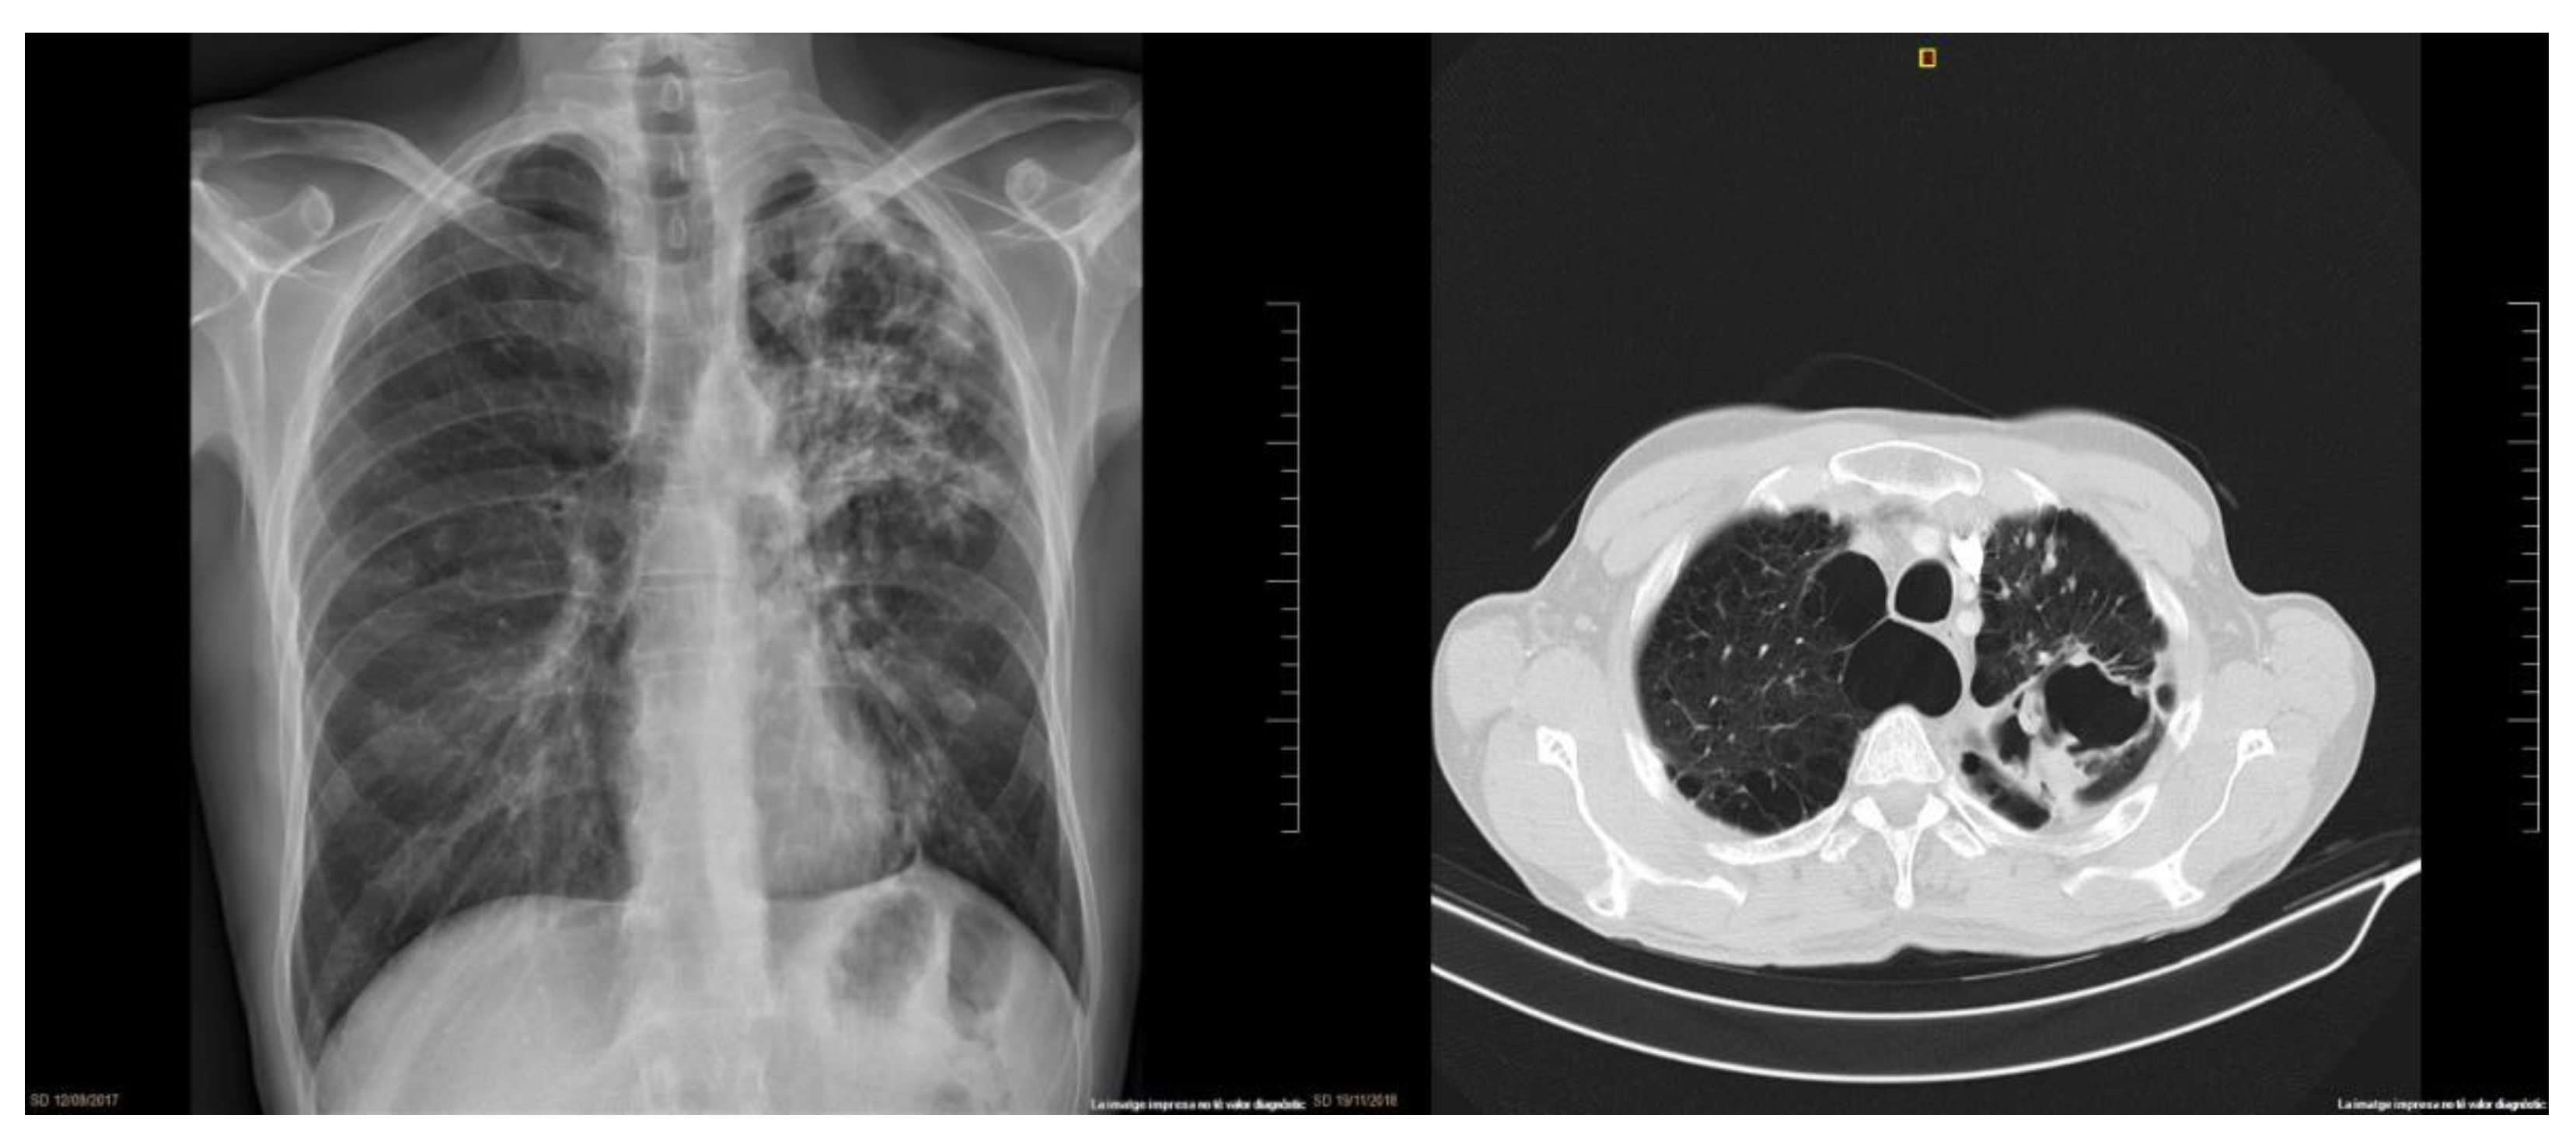

2. Clinical Case